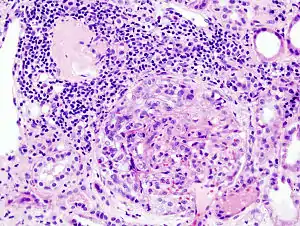

Após identificar o rápido compromisso da função renal com um exame de creatinina, ureia, albumina e hemácias no sangue e na urina é recomendado uma ultrassonografia dos rins para ver se os rins estão aumentados, biópsia renal para ver se há padrão de "lua crescente" nos glomérulos (visível em até 75% dos casos) e um exame de autoanticorpos (ANA, ANCA e Anti-GBM).[3]